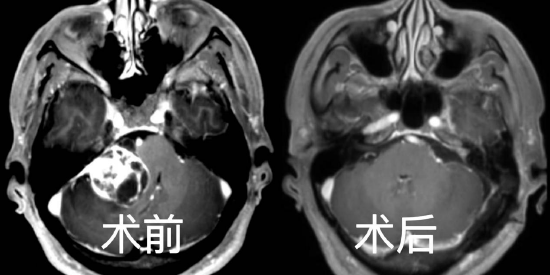

无独有偶,68岁的胡爹爹在一年前发现左侧听力下降近伴有耳鸣,但却并未放在心上,最近通过其他人了解到可能是颅内长了肿瘤引起的才重视起来,来到该院神经外科专家门诊就诊。金胜昔教授给他做了行颅脑核磁共振之后,证实为左侧听神经瘤,肿瘤大小约2.3*2.7*2.5cm。术前电测听证实左侧无有效听力。通过完善术前检查后,再神经电生理、麻醉团队护航下历经约6小时完整切除肿瘤,术中面神经保护良好,术后病理提示为听神经鞘瘤。